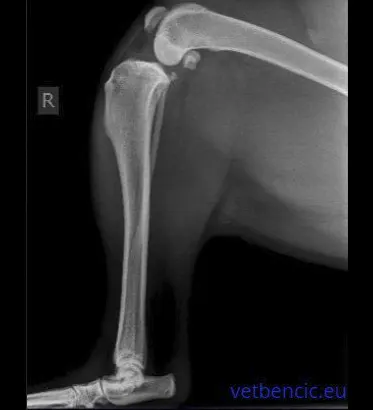

Kod sumnje na displaziju, potrebno je napraviti RTG kukova u sedaciji.

Potrebno je provesti ORTOLANI test za procjenu opuštenosti kukova, a ponekad su potrebne i napredne dijagnostičke metode kao što su CT ili MRI.

Kada je dijagnostika završena, predložiti ćemo najbolju terapiju za pacijenta.

Najbolji način liječenja displazije kuka ovisi o mnogim čimbenicima, no najvažniji je stupanj težine kliničke slike. Kod nekih pasa klinička slika je blaga, kod nekih je dijagnoza displazije slučajan nalaz, otkriven tijekom razvojnog snimanja za displaziju kukova.